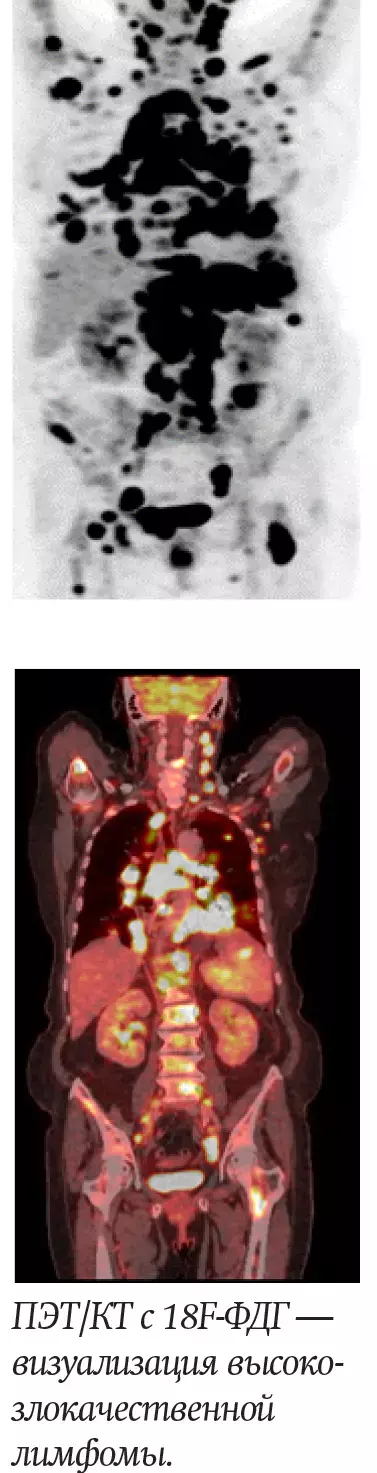

В нашей стране осуществляется радионуклидная диагностика практически всего спектра различных нозологических форм злокачественных опухолей, причем более 50 % исследований приходится на злокачественные лимфомы, рак молочной железы, рак легкого и бронхов и колоректальный рак. До настоящего времени 18F-ФДГ является самой используемой молекулой в ПЭТ/КТ-диагностике, на ее долю приходится до 90 % исследований.

Благодаря такому гибридному методу визуализации, как ПЭТ/КТ, возможно не только более достоверно оценить распространенность уже верифицированного опухолевого процесса, но и помочь в поиске первичного очага опухоли при наличии только метастазов, а также найти наиболее агрессивный участок опухоли для планирования биопсии. Кроме того, по результатам ПЭТ/КТ возможно не только планирование лучевой терапии, но и оценка эффективности проведенного лечения после его завершения.